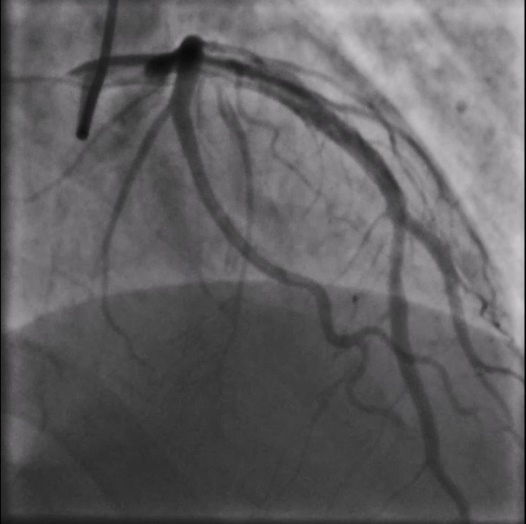

重庆江北区的65岁李先生反复心前区疼痛2年,半年前在外院前降支近端植入支架一枚,术后症状仍然反复,曾在多家医院就诊,无法明确原因。近日到新桥医院就诊,医院心血管内科为李先生安排了冠脉造影检查,结果提示:前降支支架内未见明显狭窄,但血流速度较正常冠脉明显变慢。

二维平面的造影结果不能提供更多的信息,于是,新桥医院导管室主任赵晓辉教授决定采用高清IVUS技术(HD-IVUS,high definitionIntravascular ultrasound)对冠脉内结构进一步分析。结果显示支架梁近端开口处有一低密度斑块是引起慢血流的罪魁祸首。

“传统IVUS使用40M赫兹的低频探头,而高清IVUS超声探头为60M赫兹,更高的频率带来了分辨率更加清晰的成像效果。”新桥医院心血管内科赵晓辉副主任介绍到,相较传统设计,高清IVUS使用先进的60 MHz复合传感器,提供了更均衡的组织声阻抗和更高的信号敏感度。同时配合宽频技术,高清IVUS保持了对大血管的穿透深度,轴向及侧向图像分辨率也得到了更明显优化。

新桥医院心血管内科晋军主任表示,冠状动脉血管造影术一直是评估冠状动脉狭窄程度的传统手段,然而,造影获得的二维影像并不能准确反映病变处冠脉血管内壁的病理解剖结构,高清IVUS在拥有良好的穿透深度的同时,提高了影像信号的敏感度和分辨率,较普通IVUS,能够提供更为全面细致的信息,充分发挥血管内“探路先锋”的作用,为术者制定手术策略,优化手术方案铸就更坚实的基础。